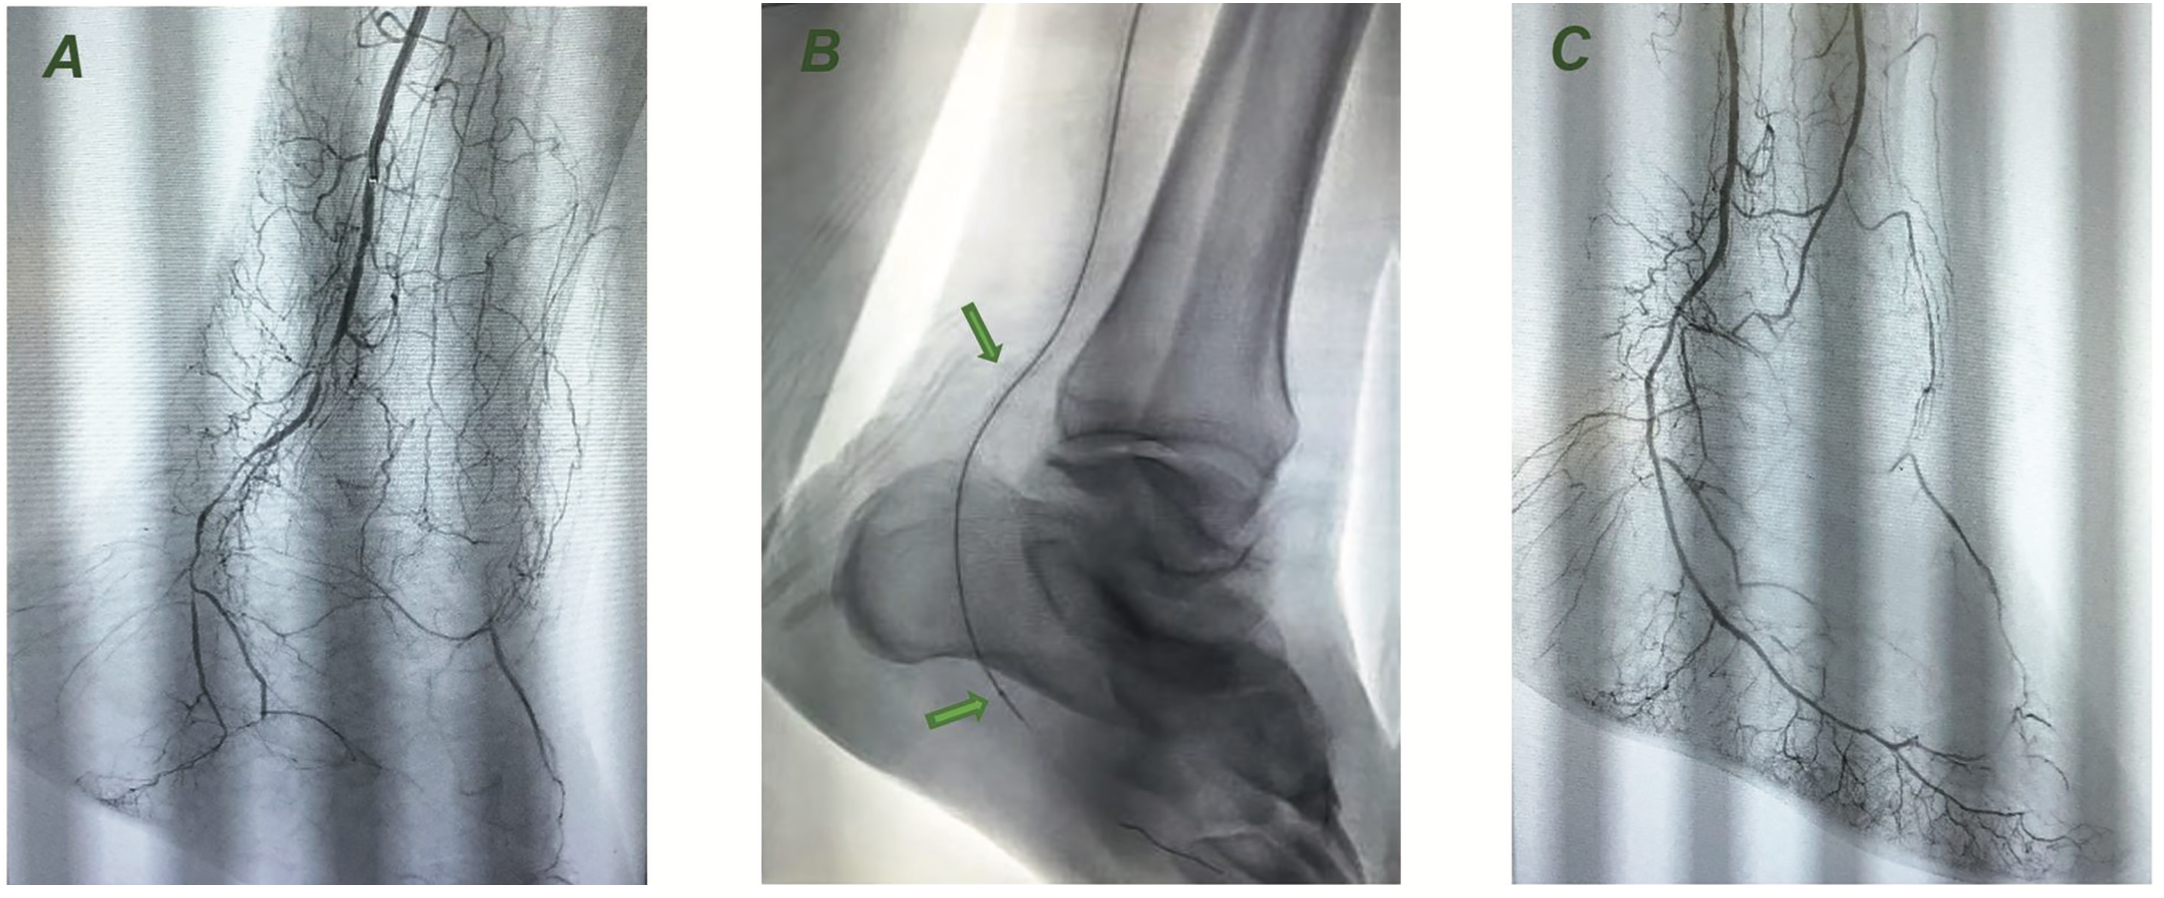

Subsequently, a 4 French Precision access sheath (Terumo) was placed. Diagnostic aortogram with runoff was obtained (Figure 1A). A summary of the angiography findings:

The patient was heparinized and activated clotting time (ACT) maintained at more than 200 seconds. The 4 French sheath was exchanged for a 6 French, 45 cm Destination sheath (Terumo). The posterior tibial artery was selectively cannulated. The stenosis and occlusion were crossed using a Glidewire Advantage .014-inch Glidewire (Terumo). The Glidewire was then exchanged for a ViperWire Advance guidewire (Cardiovascular Systems, Inc. [CSI]). Orbital atherectomy was performed on the left posterior tibial artery and the plantar artery (Figure 1B) in the foot using the Diamondback 360 peripheral orbital atherectomy system with 1.25 mm Micro Crown (CSI) (Table 1). Orbital atherectomy was followed by angioplasty using a 2.5 mm x 40 mm balloon for the posterior tibial artery and 1.5 mm x 150 mm balloon for the tarsal artery in the foot. Post procedural final angiography was performed (Figure 1C) with and without the wire, after giving 500 µg of nitroglycerin, which showed good in-line flow all the way to the toes. The patient tolerated the intervention well and there were no complications.